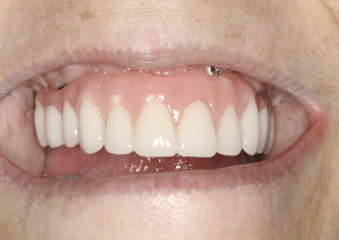

This is an unfortunate mindset in that current advances in protocol and technology can result in significant advantages in addressing some or most of these concerns. The patient shown in Figure 12 may serve to illustrate this point. She had a destroyed maxillary dentition, a less-compromised but highly unesthetic mandibular component, and a single goal: to be able to "smile at my grandchildren again." In consultation with her and her family, it was decided that a double-arch fixed implant approach would most realistically address her esthetic goals and provide her with the desired prosthetic result. She was 102 years old at the time of initial consultation. Using a staged operating-room approach, provisional restorations were initially delivered, followed by subsequent definitive hybrid final restorations. She was able to use these comfortably for the next 6-½ years (Figure 13 and Figure 14).

Fig 12. Treatment to restore this patient’s smile and functionability commenced when she was 102 years old.

Figure 12

Fig 13. An All-on-4 approach was used to treat both arches with interim immediate and eventual definitive restorations.

Figure 13

Fig 14. Final restorations used for 6-1/2 additional years.

Figure 14